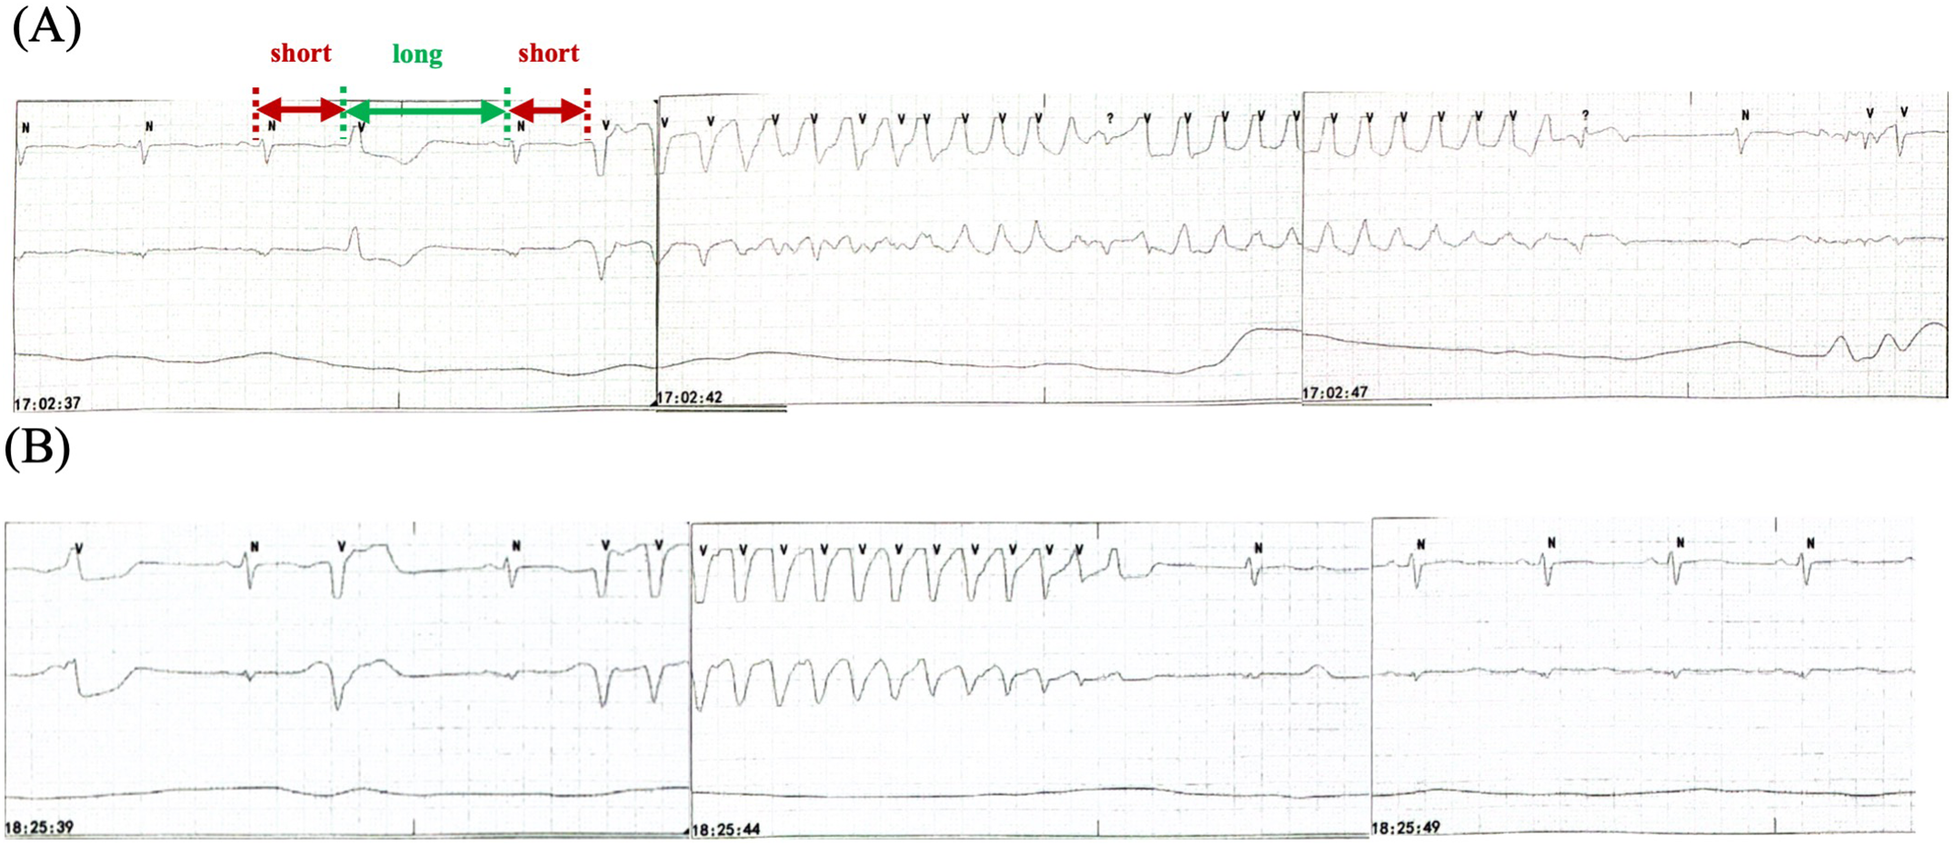

The patient underwent intubation and sedation because of hemodynamic instability caused by recurrent ventricular arrhythmias (VAs), and received intravenous magnesium and potassium supplement, which maintained the electrolyte balance rapidly (K+ 4–4.5 mmol/L, Mg2+ 1.0 mmol/L). Diuretic was administered to reduce the capacity load. QTc shortened to 558 ms and TWA disappeared after correcting electrolyte disturbance (Supplementary Figure S1). However, the patient presented with recurrent TdP (Figure 3A). The patient had no family history of dilated cardiomyopathy, ventricular arrhythmias (VAs), syncope, and sudden cardiac death. Coronary angiography ruled out obstructive artery disease 1 year ago. Her baseline ECG and UCG were normal before initiating osimertinib, with QTc of 451 ms, LVEDD of 49 mm, and LVEF of 60% (Supplementary Figure S2). There were no records of cardiac follow-up during the treatment of osimertinib. The genetic testing did not indicate pathogenic mutations. Thus, we considered acquired long QT syndrome (aLQTS) and HFrEF induced by osimertinib as the chief causes of VAs and hypokalemia as an important trigger.

Figure 3

Recurrent TdP. (A) TdP with a “short-long-short” pattern of R-R cycles (red and green arrows) before intravenous ISO administration. (B) TdP recurrence when the HR decreases to the baseline level after terminating ISO. TdP disappears for 90 min with HR >60 bpm because of the use of ISO. HR, heart rate; ISO, isoproterenol; TdP, Torsade de Pointes.

Osimertinib was discontinued. Lidocaine, which may shorten QTc interval by blocking late-sodium current, was administered but was proven ineffective. The family refused temporary transvenous pacing, and we finally agreed on intravenous ISO. Upon administering ISO at 0.5 ug/min [recommended ISO dose is 0.5–5 ug/min and target HR is 90–110 bpm per the American Heart Association/American College of Cardiology guideline (2)], the HR increased from 60 bpm to 90 bpm. Continuous ECG tests suggested shortness of QTc from 558 ms to 519 ms and improved T wave morphology (Figure 4). The recurrent TdP was terminated. However, we observed a gradual decline in systolic BP (SBP) from 120 mmHg to 85 mmHg, which was attributed to the worsened MR and decreased cardiac output index with faster HR. Thus, we terminated ISO immediately. The SBP recovered gradually, but TdP recurred when the HR decreased to 60 bpm, thus confirming the efficacy of ISO (Figure 3B). To prevent VAs and ensure hemodynamic stabilization simultaneously, we re-titrated to a low dose (0.17 ug/min) of ISO and attained stable SBP and quiet ECG monitoring with an HR of approximately 80 bpm. The TdP did not relapse. NT-proBNP gradually declined to 491 pg/ml, and repeated CXR suggested improved effusion and smaller heart shadow (Figure 2B). The patient was extubated on day 7, and ISO was terminated on day 9. Before discharge on day 21, repeated ECG suggested QTc of 509 ms and improved T wave morphology (Figure 1C). Repeated UCG indicated normal LVEDD, no MR, and LVEF of 39%.

In this case, the patient demonstrated QTc prolongation from 451 ms to 655 ms and decline of LVEF after using osimertinib 3 months. Furthermore, ECG after defibrillation demonstrated a repetitive ABABAB pattern in the morphology and amplitude of the T wave, termed TWA. It was associated with fatal arrhythmia caused by spatiotemporal heterogeneity of repolarization. Ischemia and genetic mutations did not occur. She developed recurrent TdP despite osimertinib discontinuation, correcting electrolyte disturbance and intravenous lidocaine. Overdrive pacing by a pacemaker were reported to control TdP successfully in two cases (15, 16), which was refused by the family. Similar to overdrive pacing, ISO infusion can speed up the heart, shorten the QTc interval and may terminate TdP effectively (2). To our knowledge, this is the first case reporting ISO in the acute management of osimertinib-induced VAs. An ISO dose of 0.5 ug/min–5 ug/min is recommended; the target HR of 90 bpm–110 bpm or higher may be used if TdP recurs per the guideline (2, 17). In this case, we used an ISO dose of 0.5 ug/min, which is the lowest recommended level. TdP disappeared; however, SBP declined. We titrated the infusion rate to 0.17 ug/min with ideal HR of approximately 80 bpm, which was lower than the target HR. The SBP recovered, and TdP did not recur. Higher HR caused the deterioration of hemodynamics because of severe MR. Furthermore, the baseline HR before ISO, approximately 60 bpm, was not defined as marked bradycardia in clinical practice, which resulted in QT prolongation and TdP. Nonetheless, ISO was beneficial. Thus, the baseline HR before initiating ISO and the ideal target HR had differences, thereby warranting careful observation and treatment.